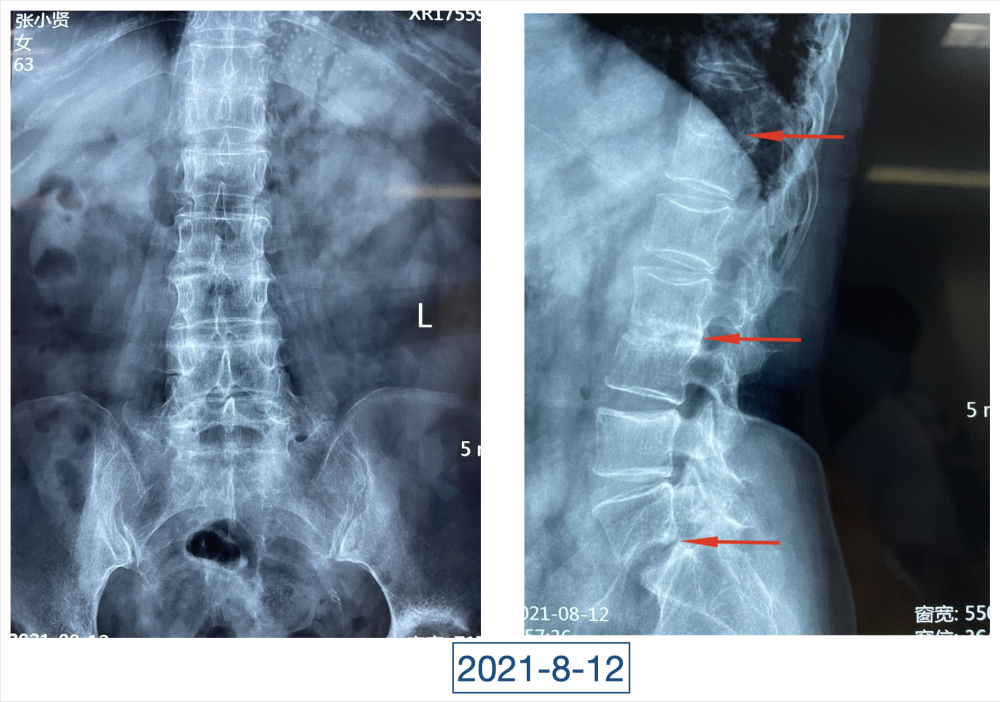

全身上下11处骨关节被破坏!密密麻麻的诊断看得李辉毫无思绪,这么久都查不出来的病因能让他查出来吗?一时间,他也说不出话。看着黄大娘深深凹陷的双眼,浑身上下几乎看不见肉,就像罩着一层饥饿的青黄色的薄皮。过了好一会儿,他叹了口气,说:“先住下吧,用药把关节疼痛缓解一下,再想办法。”

经过科室讨论、会诊,李辉也查阅了很多资料,按照黄大娘的症状,他跟之前的接诊医生一样,觉得应该是骨关节感染。可之前的穿刺、培养各种检查也做过,为什么没有找到致病菌?李辉想,或许是检查中出现了问题,没有查对地方。于是他决定,在B超引导下骨穿刺,通过最新技术精准定位病灶,只有这样也许才能抓到真正的“罪犯”。

在黄大娘入院第四天,李辉将她推入检查室,结果很快出来了,为烟曲霉菌感染。这个结果验证了李辉的想法,也解释了此前抗感染药物为何一直不奏效。“找到元凶就好办了,对症用药就可以。真菌感染本来治疗时间就很长,骨科类感染灶治疗时间更长,用了5个月的时间,终于治好了。”

近日随访得知黄大娘身体好转,李辉脸上的笑容掩饰不住,他说,据查阅文献,11处感染灶,这是全世界感染灶最多的骨关节感染,但现在,这罕见、复杂的病已经被治愈。